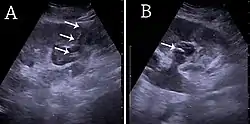

![]() (A) Ecografía renal del tubo de nefrostomía percutánea colocado a través de un cáliz en el polo inferior de un riñón con hidronefrosis. (B) El catéter de coleta se coloca en el cáliz dilatado. El tubo en (A) y la coleta en (B) están marcados con flechas blancas.[1] | ||